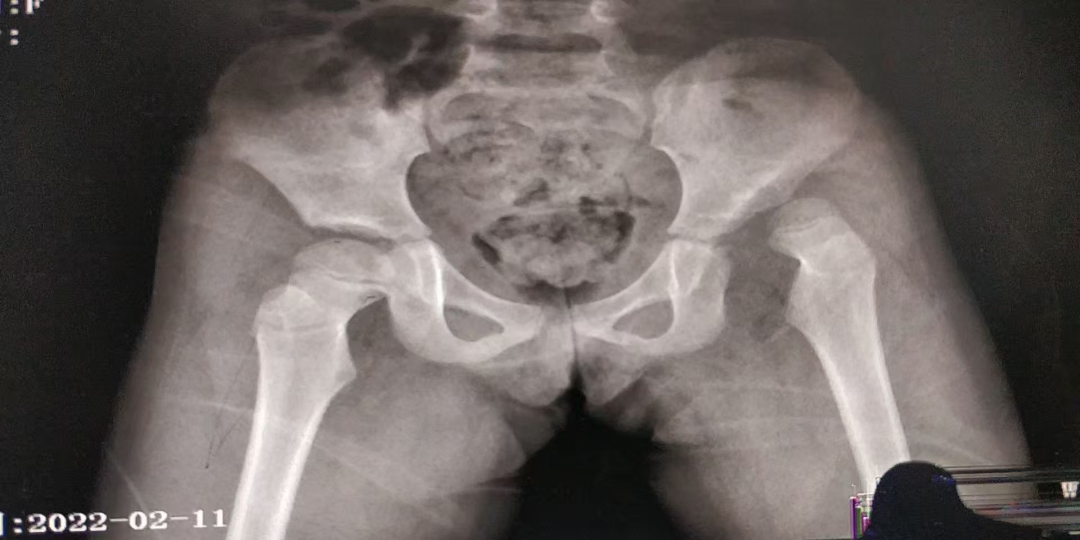

Pavlik吊带治疗髋关节发育不良(6个月内) 髋人字石膏治疗髋关节发育不良(6-18个月)

髋关节发育不良(大于18个月)切开复位股骨截骨、骨盆salter截骨